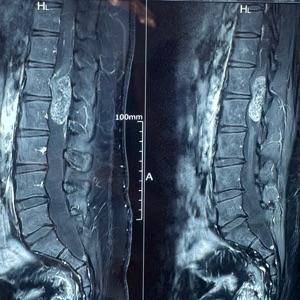

Disc prolapse, or herniation, occurs when the spinal disc's inner material protrudes through its outer ring, potentially compressing nerves. Spine surgeons address it through conservative measures like physical therapy and pain management, or surgically via discectomy, where the protruding material is removed. Techniques can vary from open surgery to minimally invasive approaches, selected based on severity and symptoms.

Spinal trauma management involves surgical and non-surgical interventions to stabilize the spine and protect neural elements. Techniques include instrumentation with rods, screws, and plates, spinal fusion, and in some cases, vertebroplasty or kyphoplasty for vertebral compression fractures. The approach depends on injury severity, location, and neurological involvement, aiming to restore spinal alignment and function.

Spondylosis, or spinal osteoarthritis, primarily involves degenerative changes leading to pain and neurologic symptoms. Treatment focuses on pain relief and functional improvement, starting with conservative approaches like physical therapy and medication. If these are insufficient, surgical options may include decompression, fusion, or disc replacement tailored to the patient's specific degenerative changes and symptom severity.